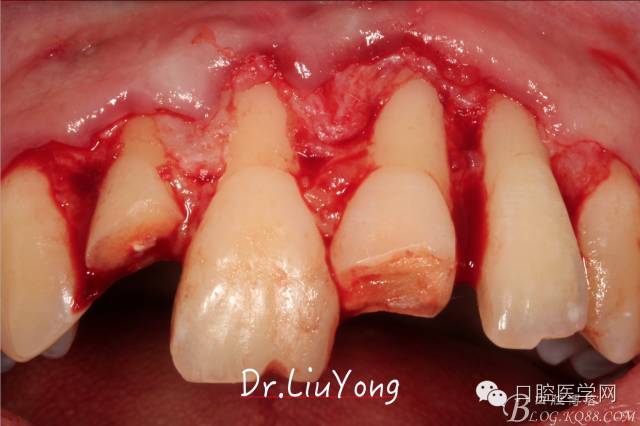

術(shù)中,可見明顯的唇側(cè)骨開裂,如上圖:

系帶手術(shù)后兩周,進行上頜前牙唇側(cè)的牙齦退縮的手術(shù)治療,由于局部附著齦缺如及牙齦厚度不足,因此同期進行上皮下結(jié)締組織移植,解決附著齦及牙齦厚度不足的問題。